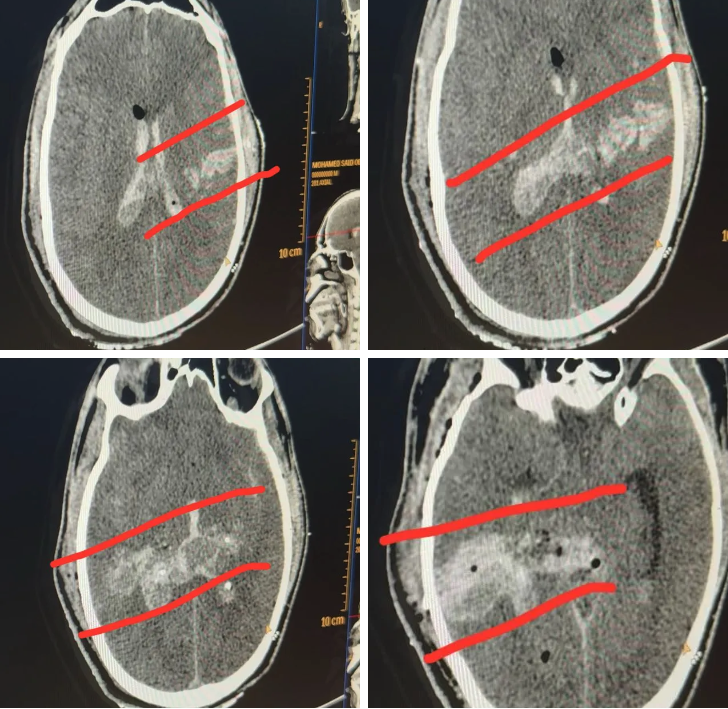

“He was brought in after an airstrike on the Mawasi tent encampment on a day when there were multiple mass casualty incidents. Some young people had been sitting at a makeshift internet cafe, including students studying for tests. Lots of patients had shrapnel injuries, but he had only two wounds, and both were in his head,” said Dr. Mimi Syed, an emergency medicine physician who has completed two medical missions to Gaza. “There was one entry and exit point, and on the CT scan it looks like a clear path. Usually with shrapnel, you’d have pieces of shrapnel still lodged inside the brain, or multiple injuries to the face. He had no other internal injuries, or injuries to other parts of the body that are common with shrapnel.”

Drop Site reviewed CT scans taken from Halimy’s injury as well as video taken of Halimy, unconscious, being intubated and treated by emergency medical personnel at Nasser Hospital. While not conclusive, the information provided suggested a gunshot wound to the head as a possible cause of death. The Israeli military did not respond to a request for comment.

Drop Site shared the scans and video with two medical experts to get secondary assessments.

“If there were no other injuries involved, it would be incredibly rare for a shrapnel injury to have such an isolated trajectory or injury. There should’ve been some other debris embedded in his body elsewhere which they likely would have seen on any x-rays that they did,” said Zain Qazi, a doctor and board certified diagnostic radiologist. “I’ve seen a lot of gunshot wounds to the head that look very similar. Sometimes the bullet is still embedded in the soft tissues or the skull, and shrapnel very likely would also have embedded itself somewhere in the bony structure or soft tissues. Oftentimes with smaller caliber bullets the bullet will fragment and have small metallic debris in the head, which we don’t see here.”

CT scan images from Halimy’s head injury. (Provided by Dr. Mimi Syed, who added the red lines.)

“These scans are highly suspicious of a gunshot wound to the head,” he added.

“The trajectory is really suspicious to be that precise,” added Nabeel Rana, another American doctor who had participated on past medical missions to Gaza. “Having said that, the typical sniper bullets we would see in these isolated gunshots would use larger calibre bullets so the exit wounds were usually pretty large.” The video, he said, did not show a clear enough view of the exit wound on Halimy’s head to make a conclusive determination, and that some small single shrapnel wounds had killed people in Gaza in his experience.Continue reading…